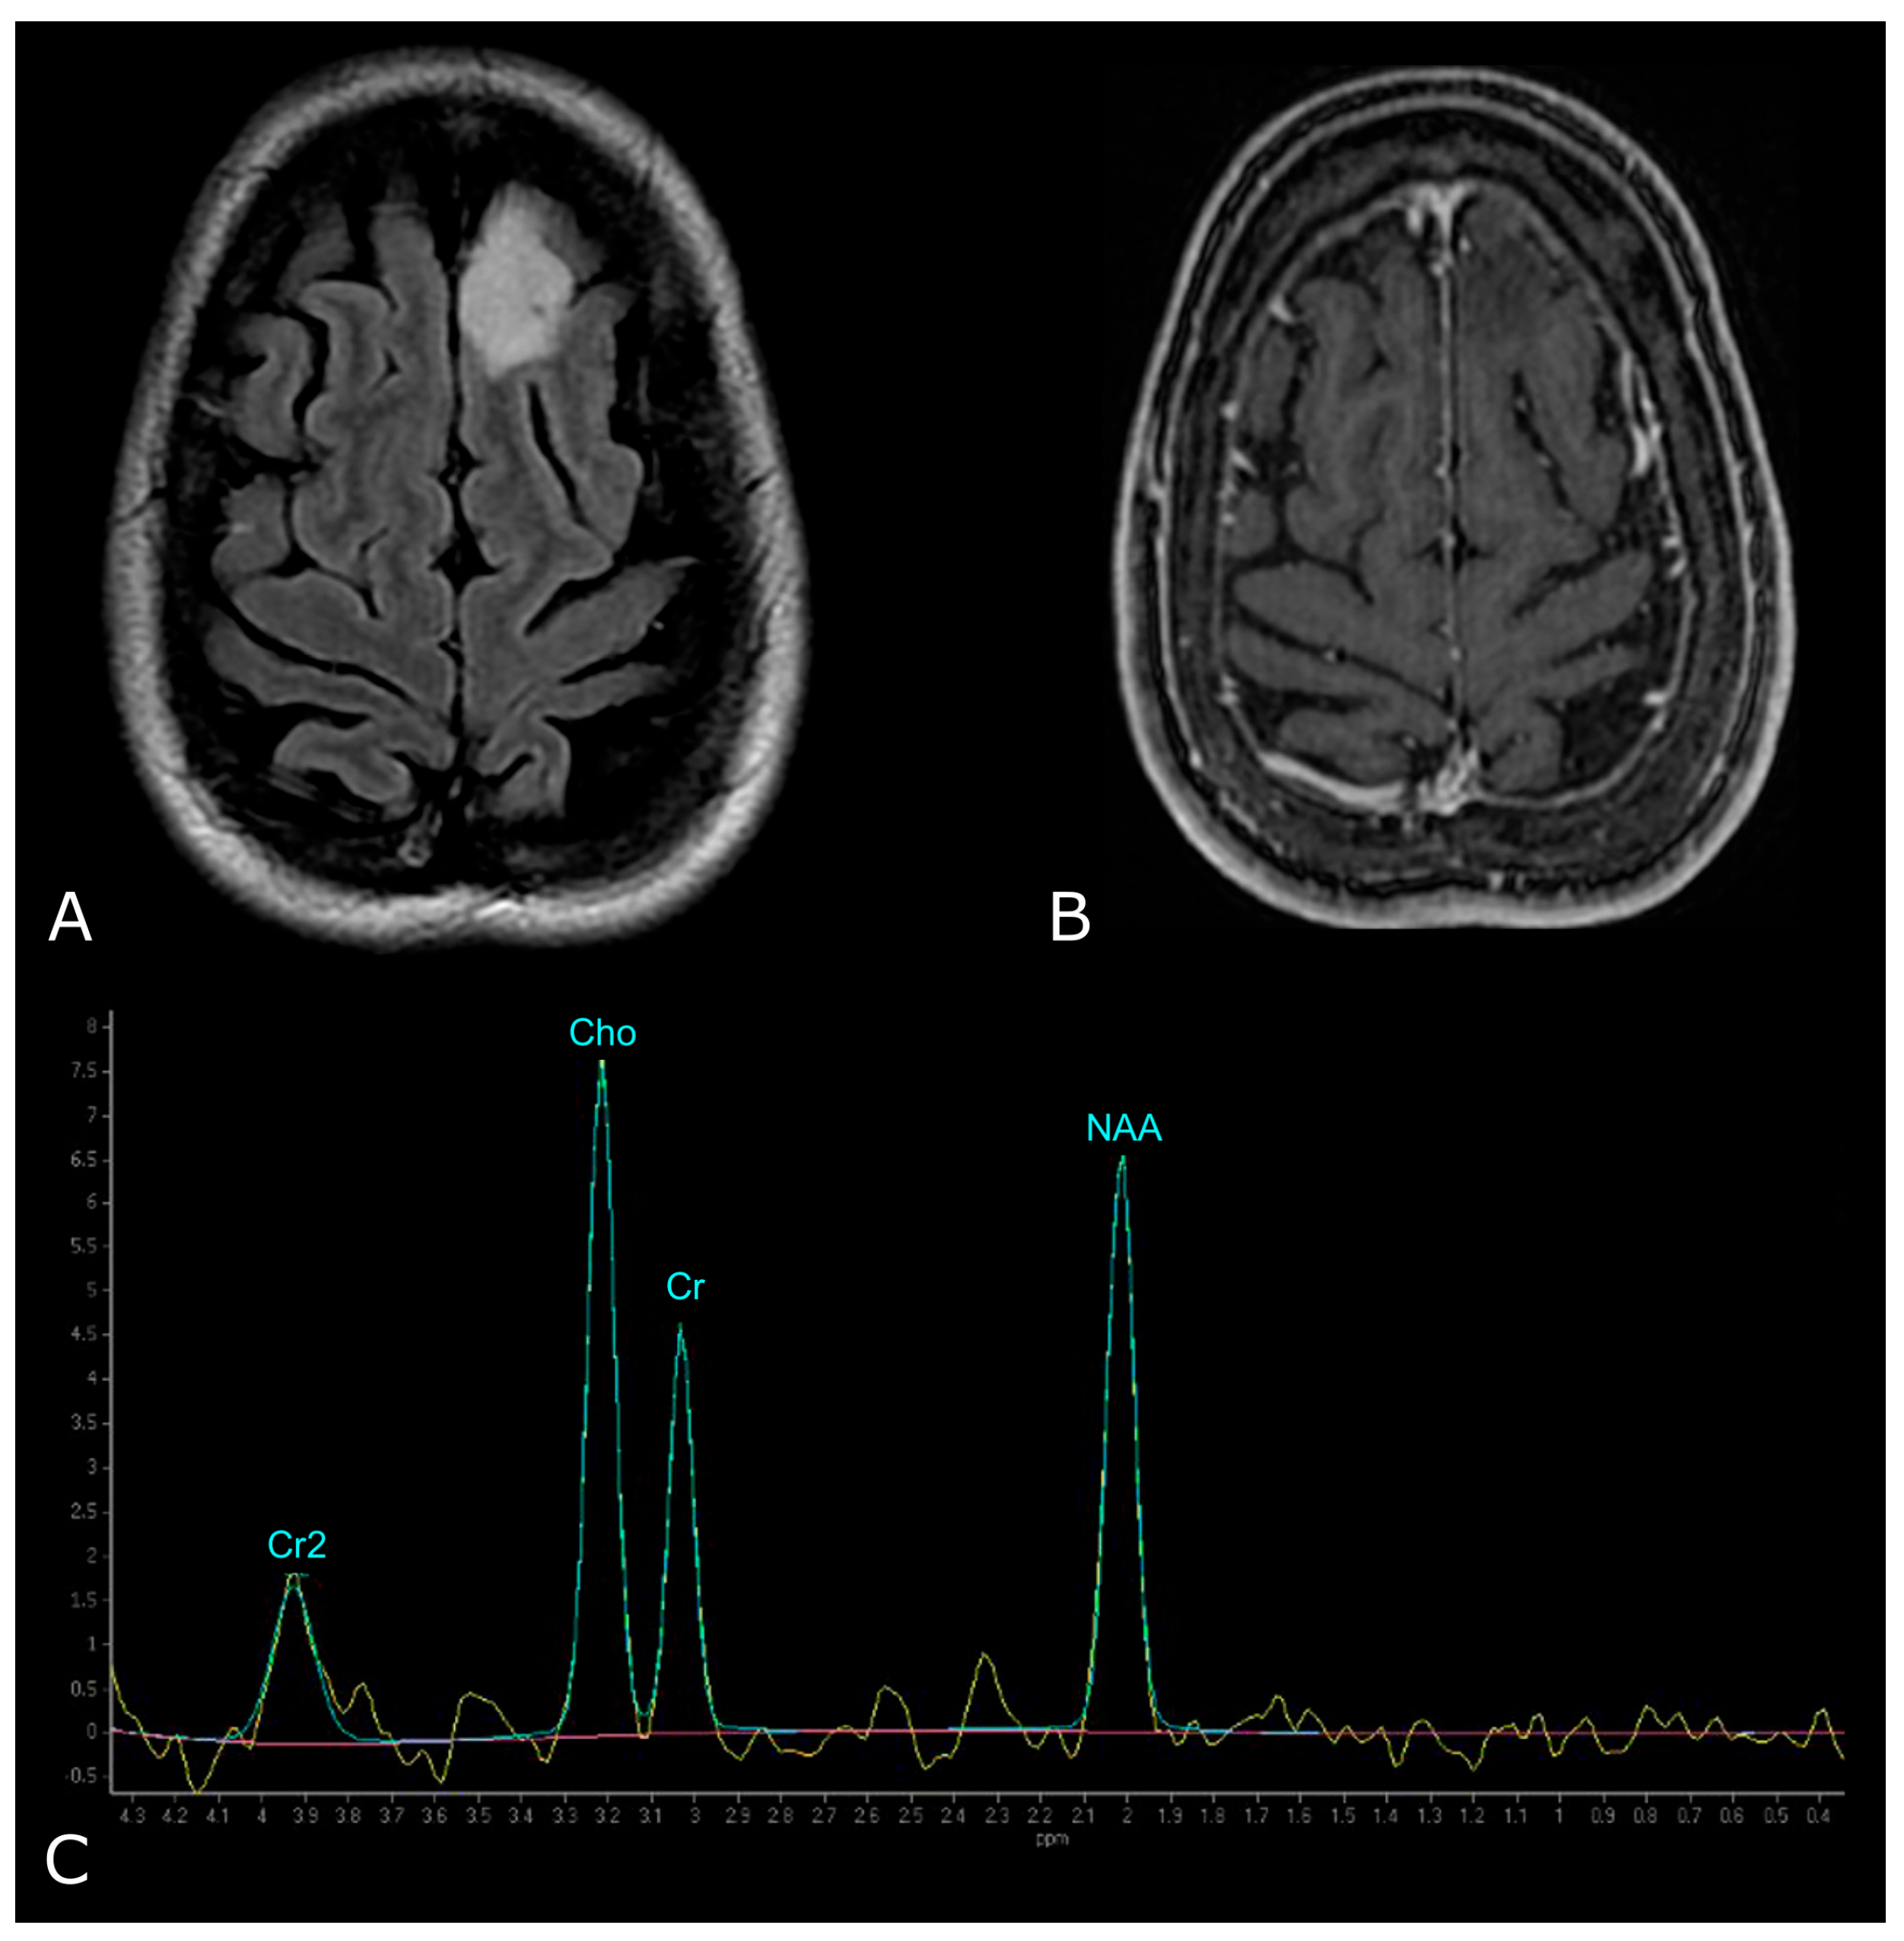

5. MR Spectroscopy

5.1. Principles of MR Spectroscopy, Metabolites and Their Function

5.2. MRS in Brain Tumors

5.2.1. Differentiating HGG from LGG

5.2.2. Prediction of Survival and Response to Therapy, Differentiating Recurrent Tumor from Pseudoprogression and Radiation Necrosis